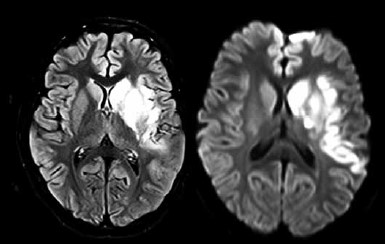

Paciente do sexo feminino, 9 anos, apresentou quadro súbito de dificuldade de fala e fraqueza à direita há 1 dia. Ao exame, apresenta afasia de expressão e hemiparesia à direita. Realizou a ressonância de crânio mostrada a seguir.

O diagnóstico é